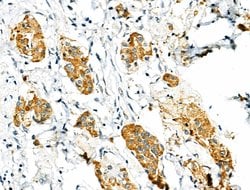

| Immunohistochemistry (Paraffin), Western Blot, Immunocytochemistry | |